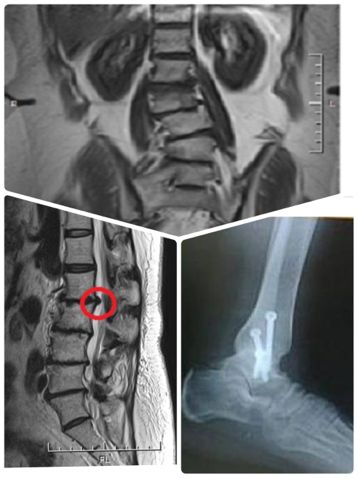

ところで、下が私の腰のMRI画像。

赤丸のようなところが椎間板ヘルニア。

その下の方の細くなったところが脊柱管狭窄症。

私の左足首の固定術の写真と一緒に、

グロテスクな写真なので、下の方に貼っておきます。